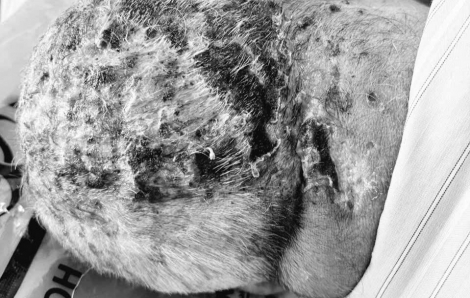

Toàn bộ vùng đầu của bệnh nhân bị loét, chảy mủ đi kèm với triệu chứng co cứng cơ khiến ông liên tục co giật, la hét vì đau đớn.

Bệnh viện Bệnh nhiệt đới Trung ương đã tiếp nhận một bệnh nhân nữ 78 tuổi (ở Bắc Ninh) trong tình trạng hoại tử nửa vùng đầu nghiêm trọng.